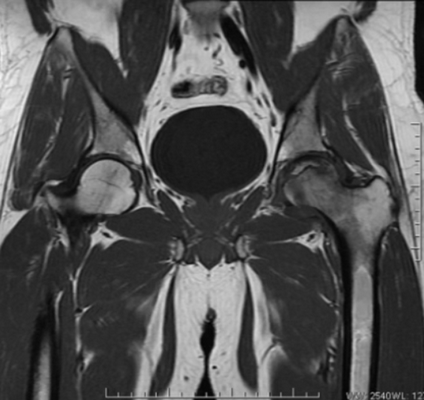

МР-скан коксофеморальных сочленений, вариант нормы

В ортопедической практике МРТ тазобедренного сустава чаще проводят для уточнения причин коксалгии - болевого синдрома в сочленении. Способ исследования не подразумевает использования ионизирующего излучения, что особенно актуально для детей и беременных женщин. Процесс создания четких снимков, которые можно увеличивать, рассматривать в объемном виде, базируется на использовании магнитного резонанса и компьютерных технологий. Для улучшения возможностей визуализации применяют контрастирование. Диагностическая ценность фото, полученных после введения гадолиния, сопоставима с результатами артроскопии - инвазивного исследования с проникновением в полость сочленения хирургических инструментов.